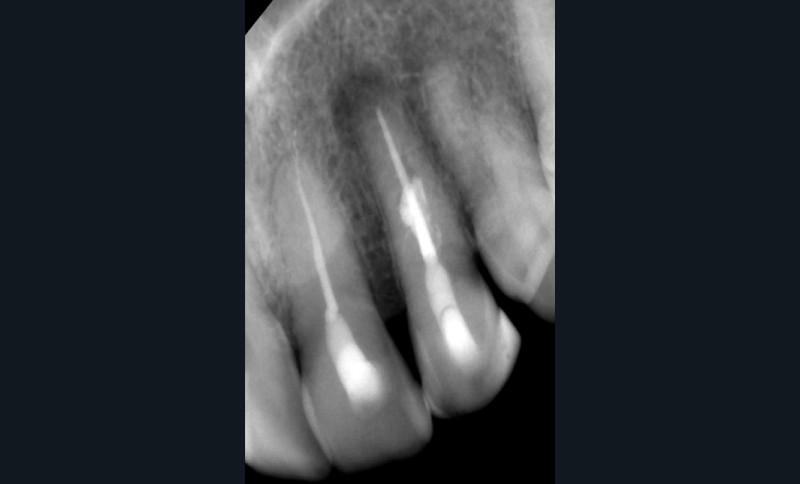

Endal, en 2011, montrait également, en utilisant le micro CT Scanner, l’insuffisance de nettoyage des isthmes inter-canalaires à nos techniques conventionnelles [19]. L’utilisation du laser Er:YAG devenait alors incontournable dans le nettoyage de ces isthmes et des zones non instrumentées (fig. 2 et 3).

Si l’étude de Peters [18] nous montre que l’instrumentation laisse 35 % du volume canalaire non instrumenté, Ricucci et Siqueira montrent que la préparation physico-chimique n’élimine que partiellement les tissus nécrotiques à l’entrée des canaux latéraux, des isthmes et des ramifications apicales, en laissant des tissus enflammés et infectés, en association avec des lésions apicales [29] (fig. 4 et 5).

Si les isthmes sont particulièrement mis en évidence au niveau des molaires mandibulaires, cela devient médicalement important au niveau des molaires maxillaires.

La diffusion bactérienne et de leurs toxines, au niveau des molaires maxillaires est à l’origine d’un grand nombre de sinusites maxillaires chroniques, d’origine dentaire. Celles-ci sont principalement causées par l’absence de traitement du deuxième canal MV, qui existe dans 90 % des cas, et il est à noter que ces deux canaux – MV1 et MV2 – sont également reliés par un isthme.

Le nettoyage des isthmes intercanalaires reste un réel problème, et semble responsable de nombreux échecs [43]. Par ailleurs, il est nécessaire d’utiliser des instruments qui évitent de propulser les débris, tant apicalement que latéralement, en obturant les entrées isthmiques avec des débris compactés.

L’utilisation d’instruments en nickel titane, tels que le XP Shaper (FKG), le Vortex blue (Dentsply) ou le Profile (Dentsply), optimise la remontée des débris et s’inscrit dans cette nouvelle philosophie. En conséquence, la combinaison XP Shaper, XP Finisher et l’irrigation avec l’Er:YAG semblent optimiser nos traitements [44,45].

Le passage du laser est répété plusieurs fois, en début, au milieu et en fin de préparation. Un protocole peut alors être proposé : 40 mJ ; 20 Hz (fig. 7). L’utilisation de biocéramiques Bioroot (Septodont) ou Total Fill R (FKG) permet de sceller le système ainsi nettoyé, en assurant une action biologique de longue durée [46] (fig. 8a à c).